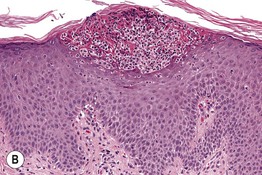

Fig. 1.10 Intraepidermal pustular dermatosis. A Pustular psoriasis. B Collection of neutrophils beneath the stratum corneum (subcorneal pustule). Scattered neutrophils are in the upper malpighian layer. A, Courtesy, Kenneth Greer, MD; B, Courtesy, Lorenzo Cerroni, MD.